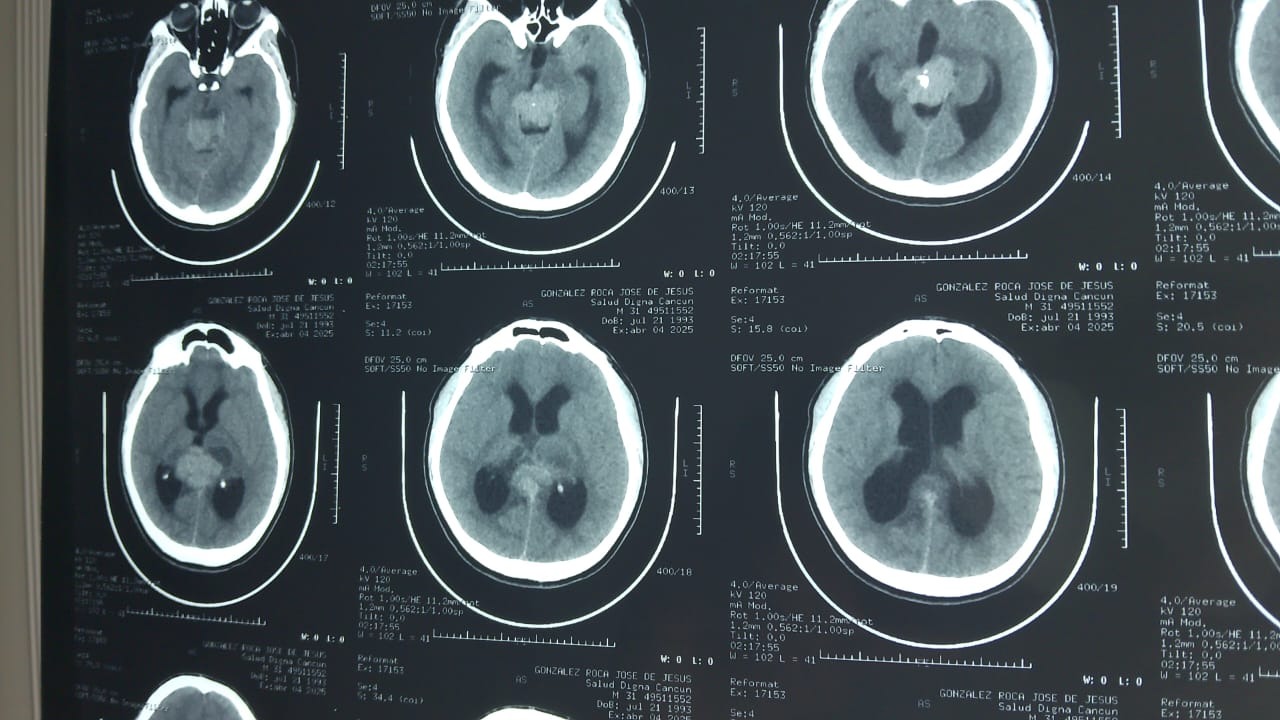

Hola, me llamo José de Jesús, tengo 32 años y vivo en Cancún, México. En abril de este año me detectaron un tumor cerebral en la glándula pineal, el cual se ha ido tratando poco a poco en el Instituto Mexicano del Seguro Social. Afortunadamente, con los estudios previos se determinó que es operable. Lamentablemente no se podrá programar en Mérida (que es lo más cercano geográficamente) hasta dentro de 6 meses más o menos, lo cual implica un riesgo de que se siga desarrollando y mi salud se vea más comprometida. Por esta razón nos vamos a ir a la CDMX para buscar otras opciones; una de las que tenemos al momento es operar con un neurocirujano particular por 100K (en pesos mexicanos) lamentablemente no contamos con esa cantidad por lo que creamos este perfil esperando tener su apoyo en la recaudación. Muchas gracias

Hello, my name is José de Jesús, I am 32 years old and I live in Cancún, Mexico. In April of this year, I was diagnosed with a brain tumor in the pineal gland, which has been treated gradually at the Mexican Social Security Institute (IMSS). Fortunately, previous tests determined that it is operable. Unfortunately, surgery cannot be scheduled in Mérida (which is the closest city geographically) for about six months, which means there is a risk that the tumor will continue to grow and my health will be further compromised. For this reason, we are going to Mexico City to look for other options; one of the options we have at the moment is surgery with a private neurosurgeon for 100,000 (Mexican pesos). Unfortunately, we don't have that amount, so we created this profile hoping to have your support in fundraising. Thank you very much.